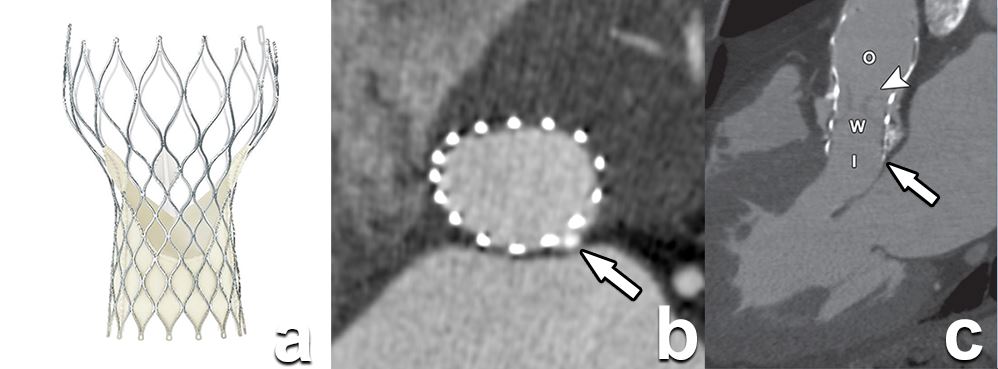

This increasingly successful method for percutaneous valve repair comes with the necessity of very precise and detailed analysis in order to plan the implant position. This can be achieved by CT and/or MRI. The European Society of Cardiovascular Radiology provides guidelines for everyday practice.

Article: CT and MR imaging prior to transcatheter aortic valve implantation: standardisation of scanning protocols, measurements and reporting—a consensus document by the European Society of Cardiovascular Radiology (ESCR)